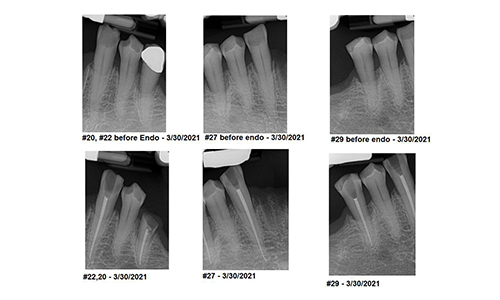

Case Report: EndoPilot Technology Expedites Multidisciplinary Dental TherapiesJuly 6, 2021

Dr. Thomas Bilski shares a case study on how the EndoPilot makes multidisciplinary care more efficient.